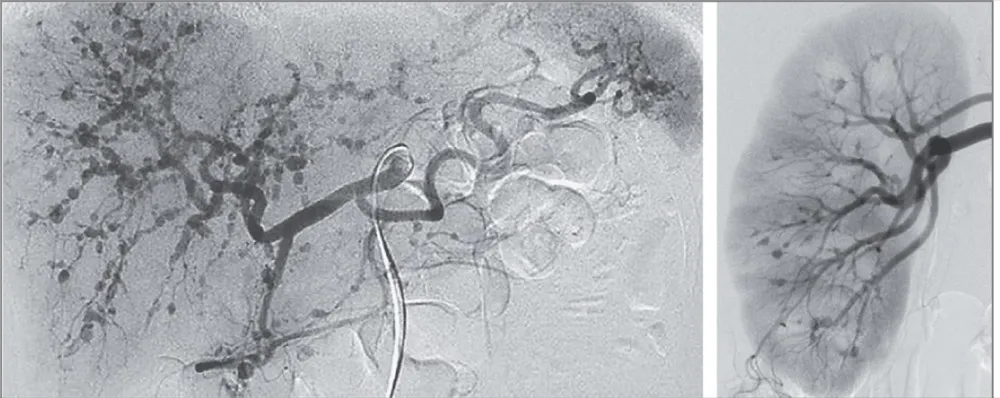

IRA + Icterícia: Um Caso que Exige Investigação Detalhada